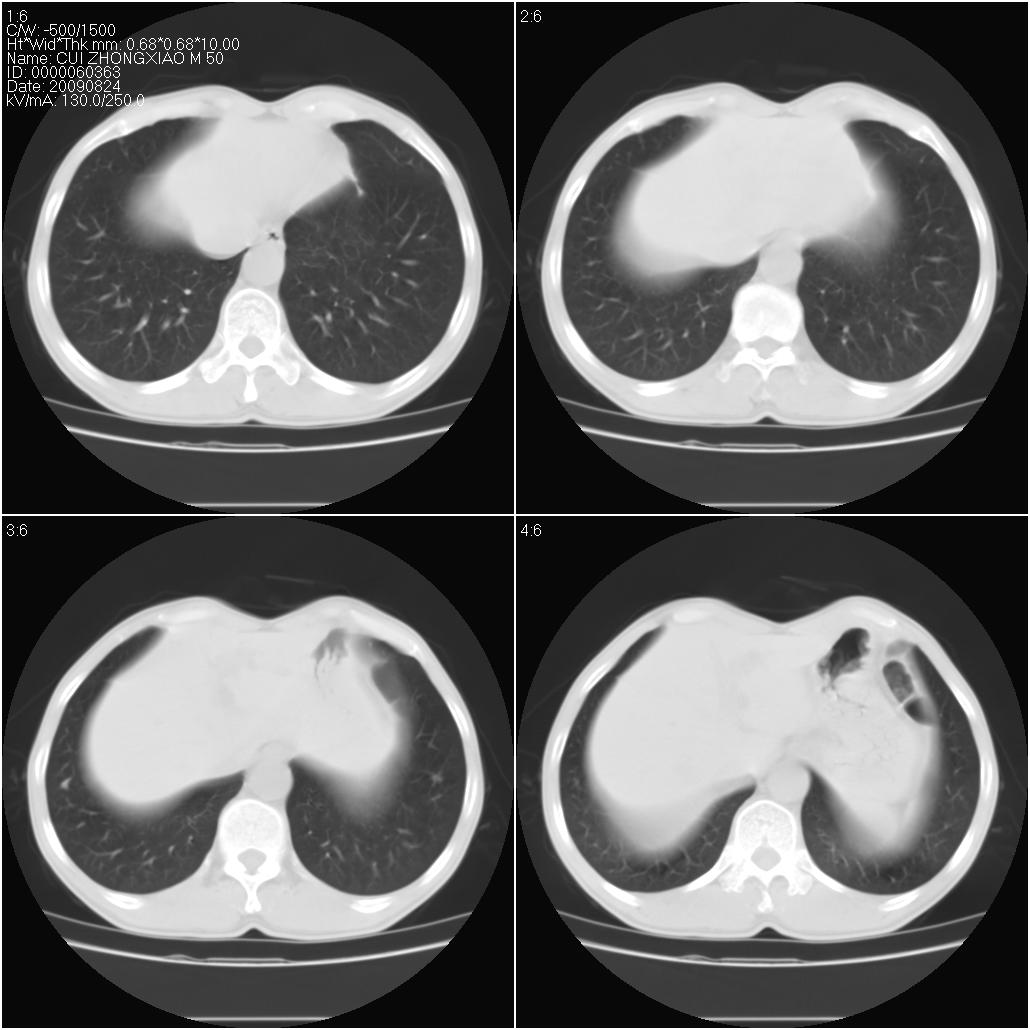

标题: CT21851:男性,50岁。间断性咳嗽半年。 [打印本页]

标题: CT21851:男性,50岁。间断性咳嗽半年。

肺泡蛋白沉着症

左侧感染!不排除局限性肺泡蛋白沉着症!

磨玻璃样改变(左肺及右肺上叶前段),边缘模糊,考虑炎症,建议严格抗炎治疗后复查除外肺泡蛋白沉积症或肺泡出血(病人有咯血吗) 肺泡癌.

肝左叶肝内胆管扩张,进一步检查.